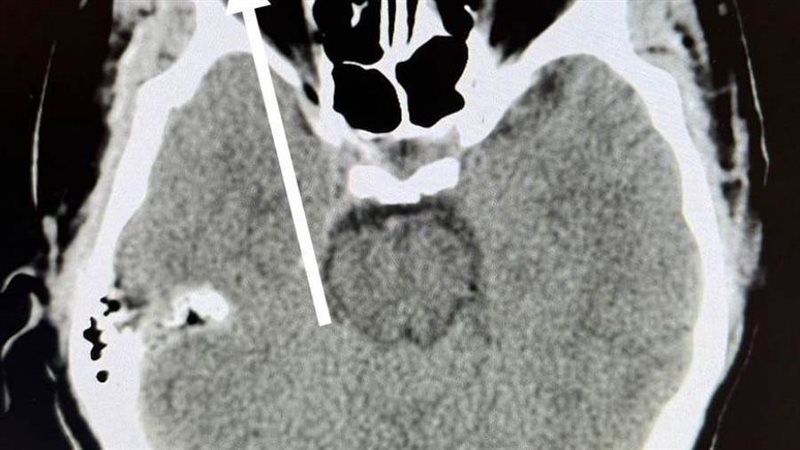

ومن جانبه، أوضح الدكتور مجدي القاضي عميد كلية الطب البشري، أن قسم الطوارئ بالمستشفي الجامعي استقبل "عامل" يعمل في تقطيع الحديد بالصاروخ بدون استخدام اي وسائل حماية مما أدي الي دخول "شظية" اخترقت جميع طبقات العين وتسببت في تهتك في القرنية والعدسة والجسم الزجاجي لتستقر في الشبكية، مشيراً الي ان المستشفى الجامعي تعد القبلة الاولى التي يقصدها جميع حالات الطوارئ من كل الجهات وعلى مدار ٢٤ ساعة بالمجان علي نفقة الدولة او الخاضعين لمظلة التأمين الصحي.

ومن جانبه قال الدكتور محمود فاروق استاذ الشبكية، أن الفريق المعالج نجح إجراء عملية دقيقة اسفرت عن استئصال الجسم الزجاجي، و الوصول الي قاع العين لإزالة الجسم الغريب وعمل كي للشبكية "بالليزر" لتجنب حدوث انفصال شبكي وتم إنقاذ عين المريض من العمي المحقق.